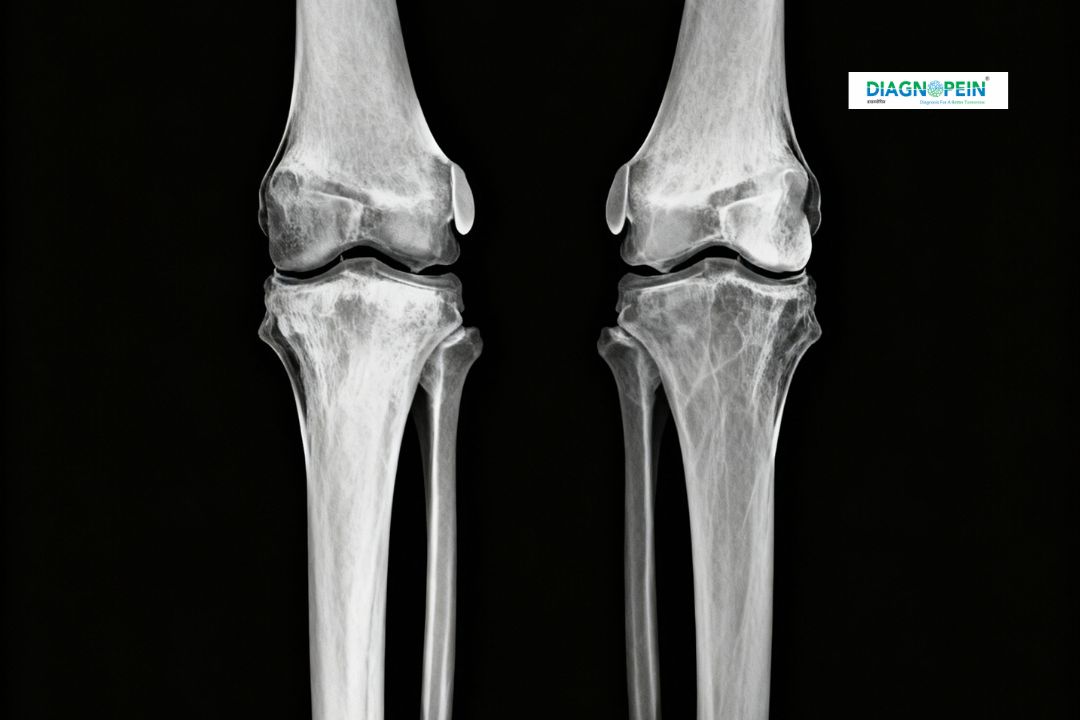

At Diagnopein Diagnostic Center in karad, X-Ray Both Knee Standing AP/Skyline View is a specialized imaging test that helps doctors evaluate the knee joints' alignment, structure, and joint space. This test uses safe radiation to produce detailed images of both knees while a person is standing. The AP (Anteroposterior) view shows front-to-back details, and the Skyline (patellar) view highlights the knee cap and the groove it moves in. It is a crucial diagnostic tool for identifying early signs of arthritis, fractures, joint deformities, and cartilage wear.

The X-Ray Both Knee Standing AP/Skyline View offers real-time insight into the knee’s weight-bearing condition, helping orthopedic specialists assess how your knees perform under natural standing pressure.

Standing X-rays help doctors analyze the knee while supporting full body weight, offering a more accurate assessment than sitting or lying X-rays. This real-life positioning helps in identifying conditions that may only appear when the knee joints are in motion or bearing weight.

The Skyline view, in particular, is ideal for assessing patellar misalignment or dislocation, while the standing AP view reveals how both knees align with the hips and ankles, giving a complete biomechanical picture.